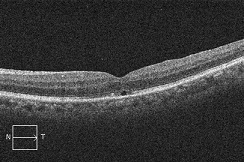

?手術の効果で、青や緑の網膜を中心部に引き寄せます。

?青の部分の網膜が、視野の中心部の視界を担うようになります。

赤に比べて、青の網膜は、視細胞の数も能力も乏しくなります。この青の網膜が中心部の見え方を担当するようになるので、どんなに回復しても「視力が悪い」、「感度が悪い」、「少し暗く見える」などが残り、完全に元通りという事はあり得ないのです。

また、中心部にギュッと網膜を引き寄せた感じになるために、基本的には「ゆがむ」「物が小さく見える」などの症状も残ります。